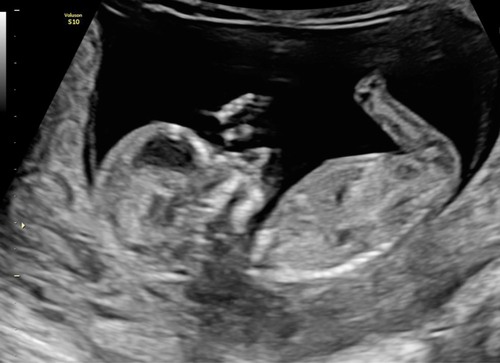

Hier ook goede echo met 13+5 zo blij!! Als iemand wil raden of het een jongetje of meisje is: ik ben heeel benieuwd wat jullie denken, moet nog even wachten tot de geslachtsecho op 5 januari.